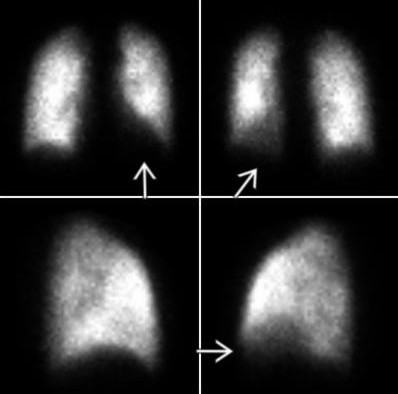

VQ Scan

Principles, Indication, and Examples

Evaluation of PE

- Ventilation: Xenon gas / DTPA

- Perfusion: 9mTc labelled microspheres or MAA

- Look for mismatched defects